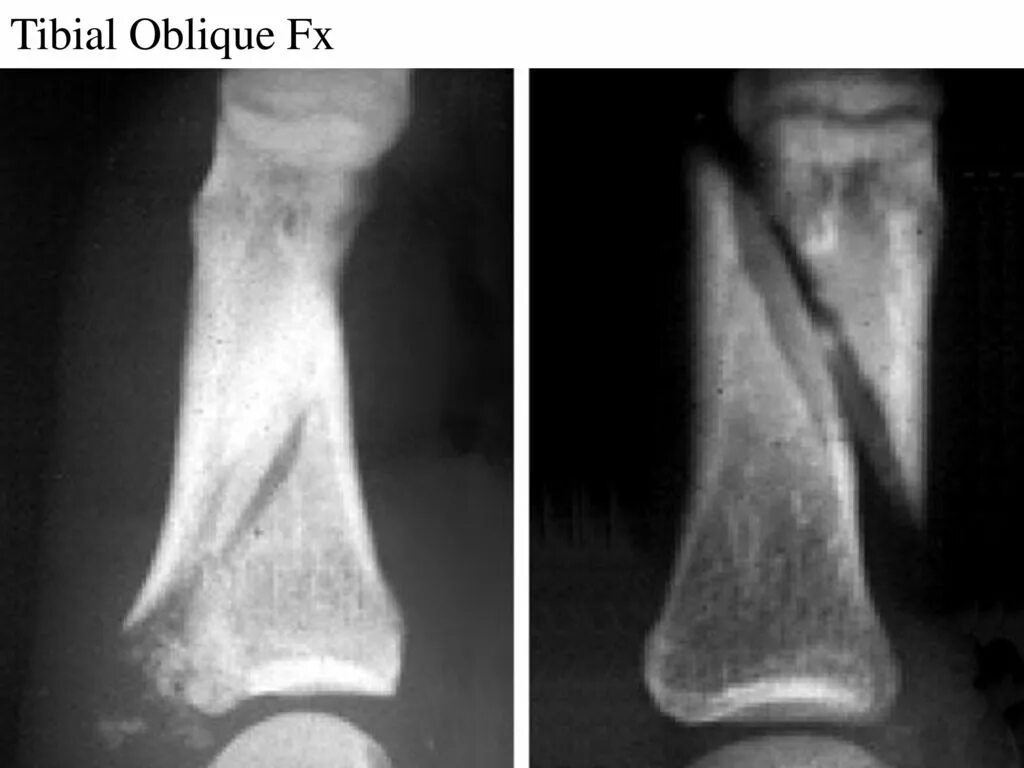

Заросший перелом со смещением